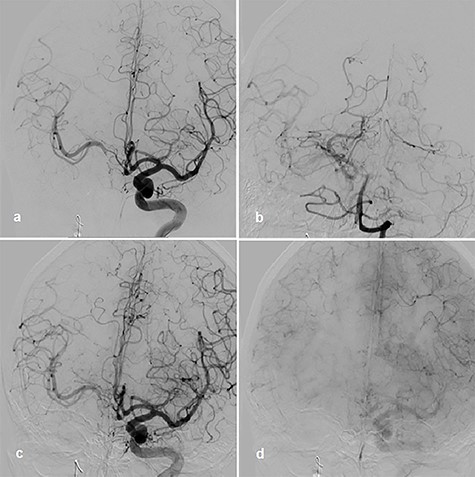

A 56-year-old woman without significant prior medical history presented with ptosis on the right side as a sign of external oculomotor palsy. Magnetic resonance (MR) imaging investigation confirmed a large mass lesion of 30 mm in diameter parasellar on the right side without perifocal edema. In MR angiography, we suspected a giant aneurysm of cavernous internal carotid artery (ICA). In the digital subtraction angiography (DSA), a giant cavernous part ICA aneurysm with wide contact to parent vessel was confirmed (Fig. 1a–d). We decided on treatment by vessel reconstruction using Pipeline™ flow diverter stent. This treatment failed after incorrect unfolding of the sheet stent in the curved part of the vessel just proximal to aneurysm neck. Several attempts to unfold the stent failed. For this reason, the intervention had to be terminated without success.

Right cavernous ICA Aneurysm on MR TOF angiography (a); DSA 3D angiogram (b); p–a projection angiogram (c); lateral angiogram (d).